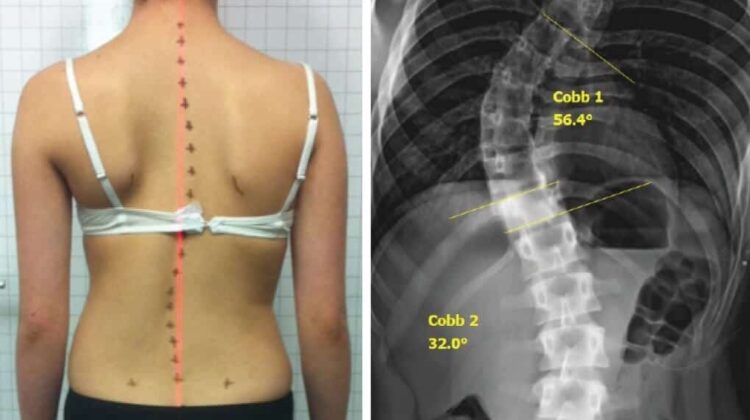

اعوجاج العمود الفقري هو انحناء جانبي غير طبيعي في العمود الفقري، يظهر غالبًا عند النظر إلى الظهر من الخلف. في الوضع الطبيعي يكون العمود الفقري مستقيمًا من الخلف، بينما تكون الانحناءات الطبيعية من الجانب فقط.

الطبيب يقوم بالفحص السريري وقد يطلب أشعة سينية لقياس زاوية الانحناء وتحديد شدته بدقة.

درجة الانحناء